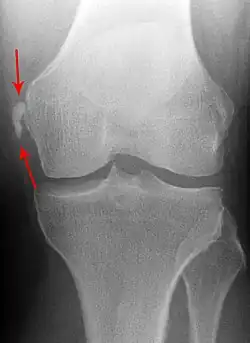

Der Stieda-Pellegrini-Köhler-Schatten ist eine Verknöcherung im Ursprung des Innenbandes des Kniegelenkes. Er ist röntgenologisches Zeichen einer stattgehabten Verletzung ebendieses Bandes. Das hierdurch verursachte Hämatom verkalkt und erscheint als knochendichter Schatten im Röntgenbild. Hiervon abzugrenzen ist der viel seltenere knöcherne Ausriss des Bandes.